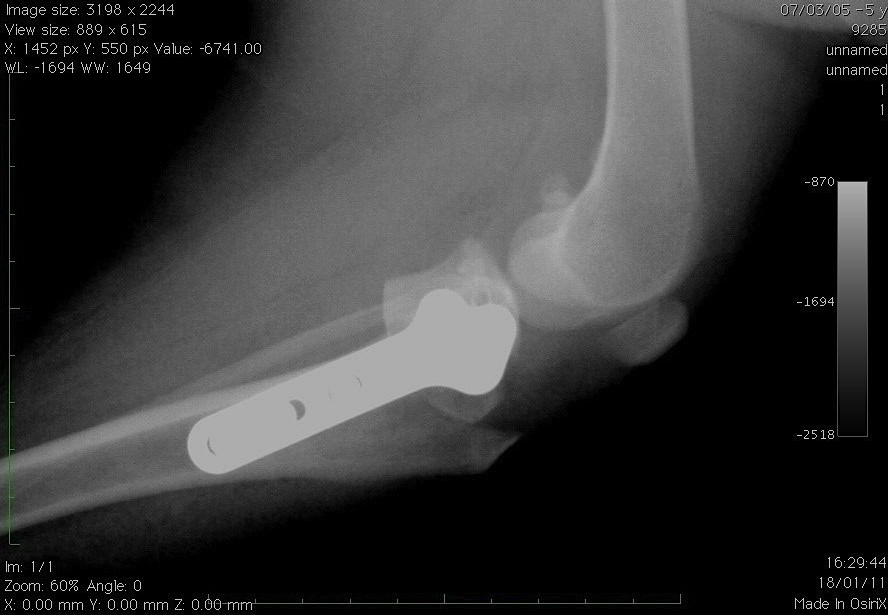

- reconstructive surgeries during broken bones limbs with the use of pins, plates and screws.

- The treatment of pathologies of the elbow or of the shoulder (elbow dysplasia, osteochondritis of the shoulder, etc.).